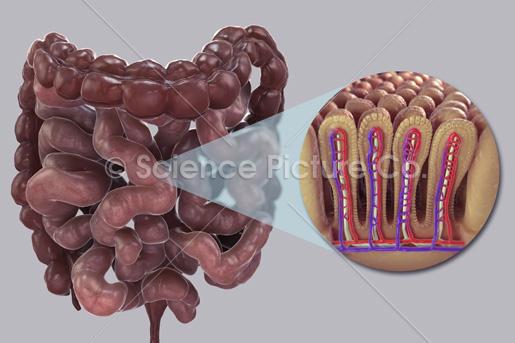

Ascending/transverse/descending/sigmoid colon

Cecum

Goblet cells

Haustra

Ileum

Inner circular layer (of muscular externa)

Jejunum

Lacteal

Lumen

Microvillus (s.) Microvilli (pl.)

Mucosa

Outer longitudinal layer (of muscular externa)

Rectum

Submuscosa

Taeniae coli

Vermiform appendix

Villus (s.) Villi (pl.)